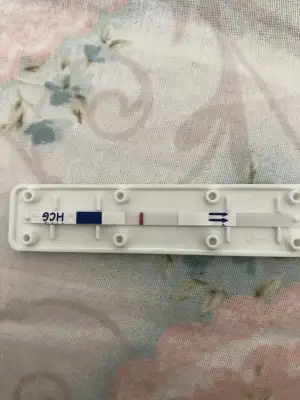

Test yaptım yine silik çıktı canım

Hayırlı olsun canım rabbim sağlıklı birşekilde kucağına almayı nasip etsinMerhaba , sizce gebe miyim silik bir çizgi cikti , ve gecikeli 3 gün oldu daha belirgin olması gerekmez mi.